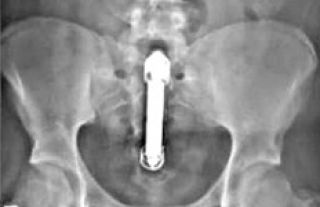

El hecho es que morimos de vergüenza antes de mostrarnos penetradxs. Y es literal. El 13 de agosto, Crónica publica que Nigel Willis, un británico de 50 años, se introdujo un vibrador en el ano durante una noche de sexo y se perforó el intestino. Estuvo cinco días con el objeto dentro de su organismo. Con mareos y malestar, se negó ir al hospital. Atormentado por el pudor, tuvo una infección generalizada y finalmente murió, según las pericias forenses, con el vibrador dentro. El accidente fue silencioso, su muerte también silenciosa, y así se mantuvo por más de un año. A partir de la judicialización, el caso salió a la luz para convertirse en motivo de chiste y asociaciones con otros mitos de protagonistas anónimxs: a la prima de una amiga se le quedó pegada una salchicha congelada, el hermano de mi jefe se atoró con la tapa del desodorante, un paciente tuvo un contraparto con una lamparita de bajo consumo, el novio de un compañero del gimnasio se abotonó con el cuerpito de una Barbie, o las camillas repletas de pacientes con pepinos y zanahorias incrustadas. Muchas personas, todxs NN. Nadie tiene nombre. Es que parece mejor banalizar los placeres del culo que llorar los muertos de la vergüenza social.